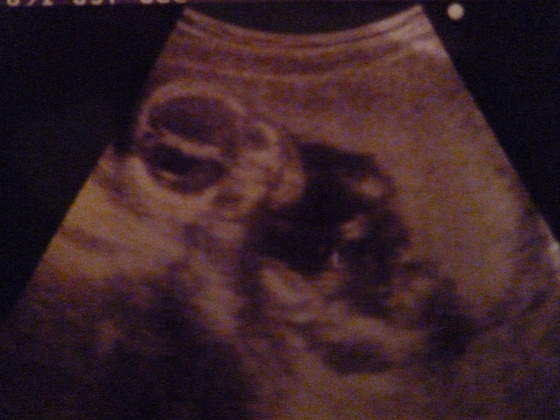

a o to moje maleństwo w 16t i 3d

zerka na mamusię![]()